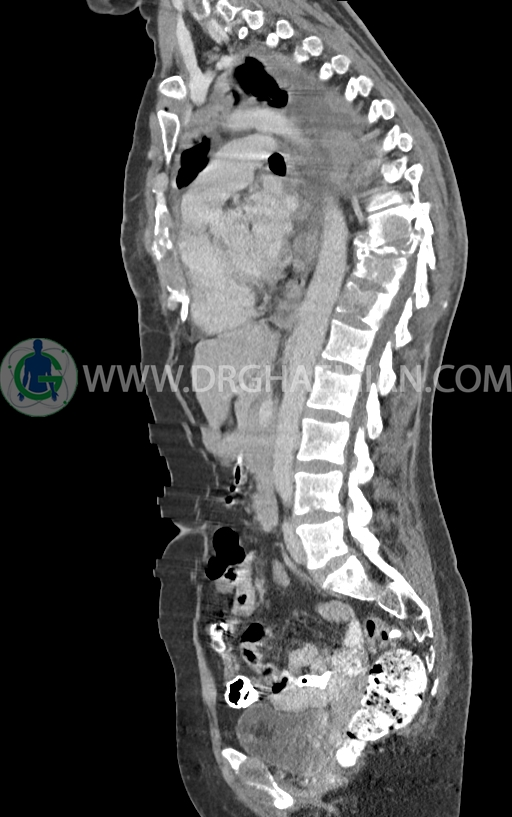

در سی تی اسکن اسپیرال ریه و مدیاستن -شکم و لگن با کنتراست خوراکی و وریدی (مولتی دیدکتور 16 با مقاطع ظریف و بازسازی های ساژیتال و کرونال) :

–توده نسج نرمی بسیار بزرگ به حداکثر دیامتر 82mm همراه با مارژین لبوله در پستان راست دیده شد که همراه با گسترش و درگیری پوست و نیپل بوده و مطرح کننده ضایعه تومورال و بدخیم می باشد.

–این توده در قسمت هایی عضله پکتورالیس این سمت را abut کرده است.

– ندول های نسج نرمی اقماری متعدد در مجاورت فوقانی این توده با حداکثر دیامتر کمتر از 17mm

– تعدادی لنف نود هتروژن و irregular با حداکثر SAD<12 در آگزیلاری راست

–ضایعات استخوانی لیتیک فراوان منتشر در تمامی طول ستون مهره و لگن رویت شدند که مطرح کننده متاستاز استخوانی می باشند.